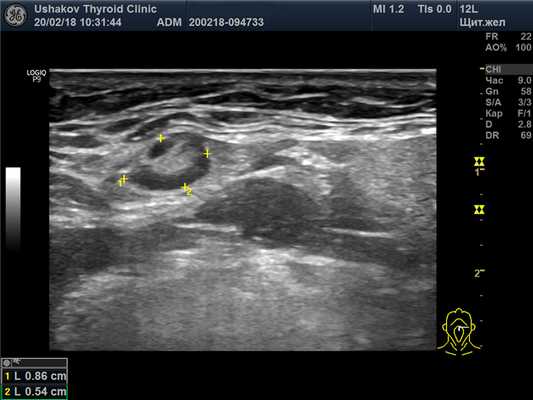

| Рисунок 4. Узел верхней (краниальной) части правой доли щитовидной железы (ограничен желтыми метками). Признаки рака узла: 1) неправильная форма, 2) неравномерный край узла, местами прерывистая граница, 3) значительно гипоэхогенная (темная) зона внутри узла, постепенно переходящая в остальную ткань, 4) микрокальцинаты. Класс по TI-RADS соответствует 4С. | Рисунок 5. Изменённый регионарный лимфатический узел. Отношение сторон меньше коэффициента 2 (округлый), внутри определяется значительное разрастание ткани (признак метастазирования). |